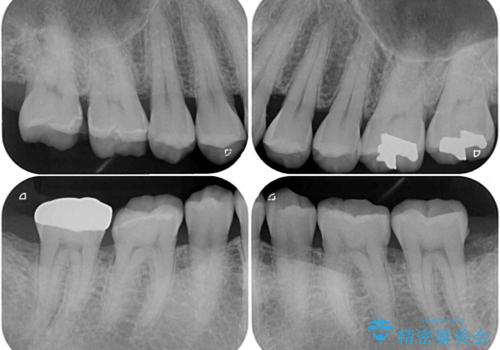

奥歯の歯間部の歯肉が炎症で赤黒くなっており、歯周ポケットを検査したところ、6-8mm(正常では3mm以下)であり、外科処置が適用となる状態でした。

まずは仮歯に置き換え、歯周ポケットを除去するための外科処置(歯肉弁根尖側移動術)を行い、治癒を待ってセラミッククラウンにて補綴治療を行うこととしました。